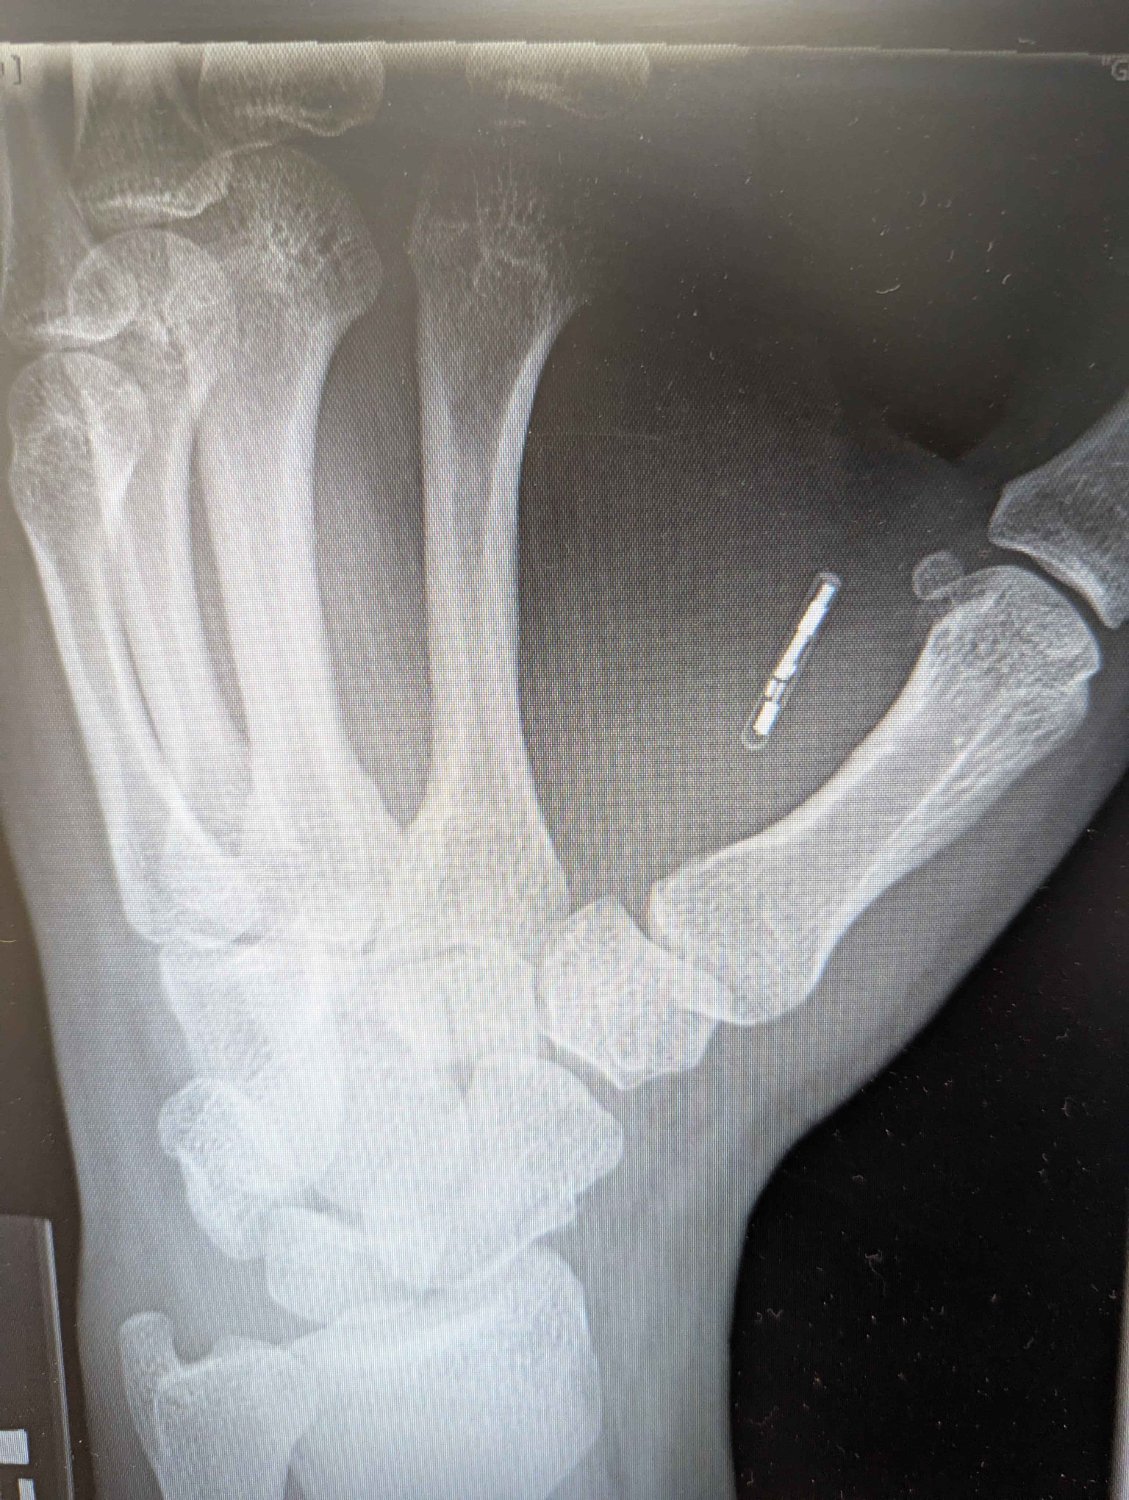

Yep, my hand. Happened to break that wrist. And no, you can’t feel it at with just that hand. Sometimes I do fidget with it through my skin using my other hand though. Mostly just cause I’m a geek and thought it would be cool to have it for building access. Mine is an RFID/NFC combo, which is why it’s bigger than the one in the article.